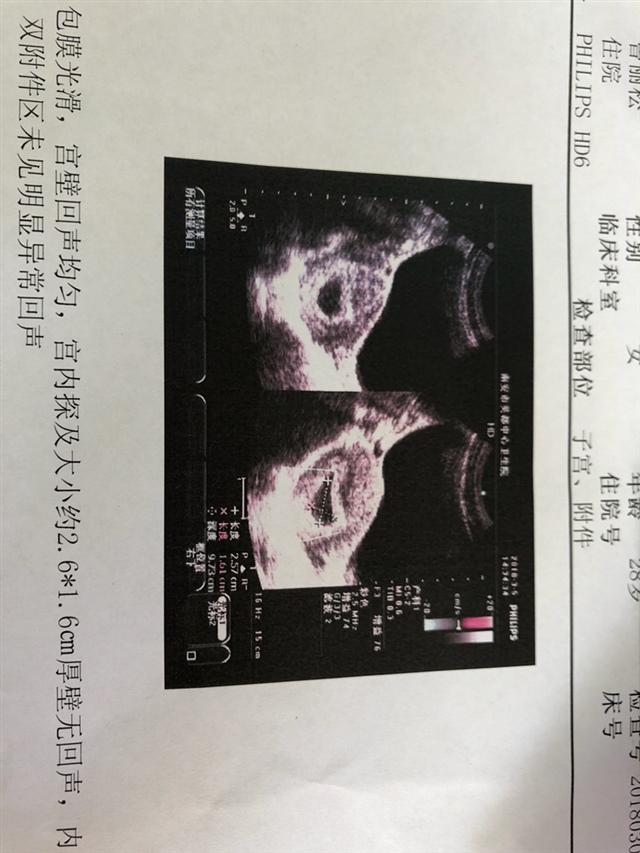

孕19周+2天